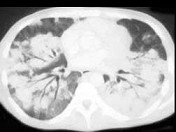

- 单项选择题女,26岁, 全身不适,发热, 咳嗽,咯血, 有吸毒史,结合CT图像, 最可能的诊断是 ( )

A、卡波济肉瘤

B、肺癌

C、肺转移癌

D、肺结节病

E、肺结核